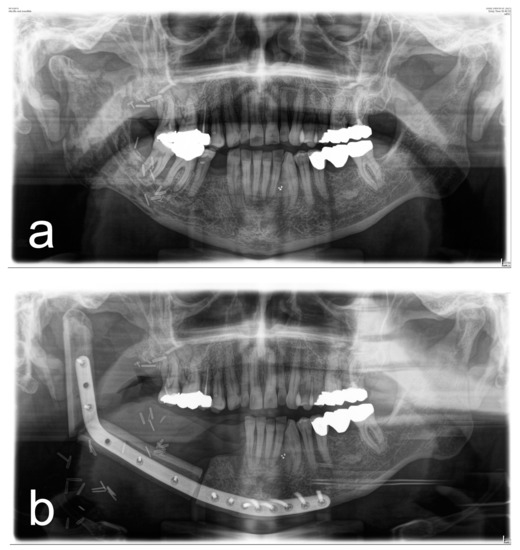

Figure 1, Figure 2, Figure 3 and Figure 4 illustrate two cases of advanced mandibular resection with severe hard and soft tissue injury followed by reconstruction using a vascularized fibula flap. This graft allows reconstruction of bone and soft tissue, the latter of which can be used to replace extraoral skin (Figure 2) or intraoral mucosa (Figure 4).

Figure 1. (a) Panoramic X-ray of a patient with extensive ORN of the mandible. (b) Postoperative panoramic X-ray of the same patient after ablative and reconstructive surgical therapy of ORN using a vascularized 2-segment fibula flap with intraoral soft-tissue transfer and patient-specific implant.